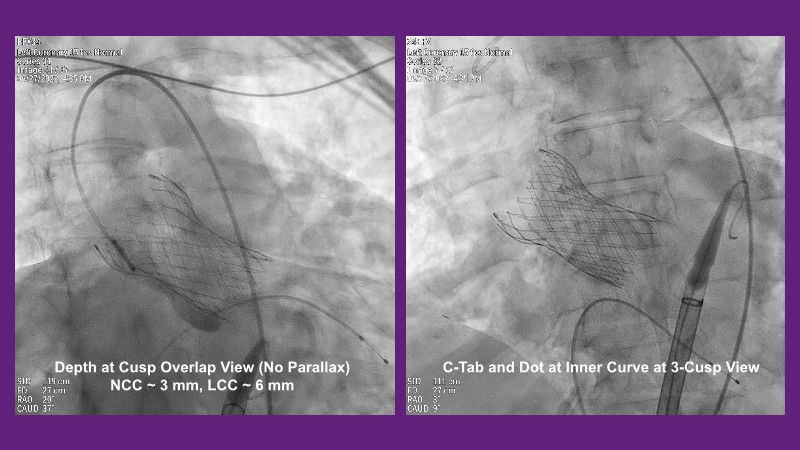

Don’t miss this PCR Tokyo Valves 2025 session replay, where leading experts share key techniques for simplifying and optimising TAVI procedures with the Evolut device. This session covers essential insights into safely performing procedures on patients with various anatomical types using the self-expandable valve, while emphasising the importance of long-term patient care and outcomes. Discover valuable strategies for surgical explantation of transcatheter aortic bioprostheses, coronary cannulation, and commissural alignment post-TAVR. Learn expert tips for streamlining procedures, such as semi-rapid pacing, using Dryseal long, and skipping pre-BAV to improve TAVI results. Watch now to stay ahead in the field!

- To understand how the self-expandable valve can be used to safely perform procedures on patients with various anatomy types